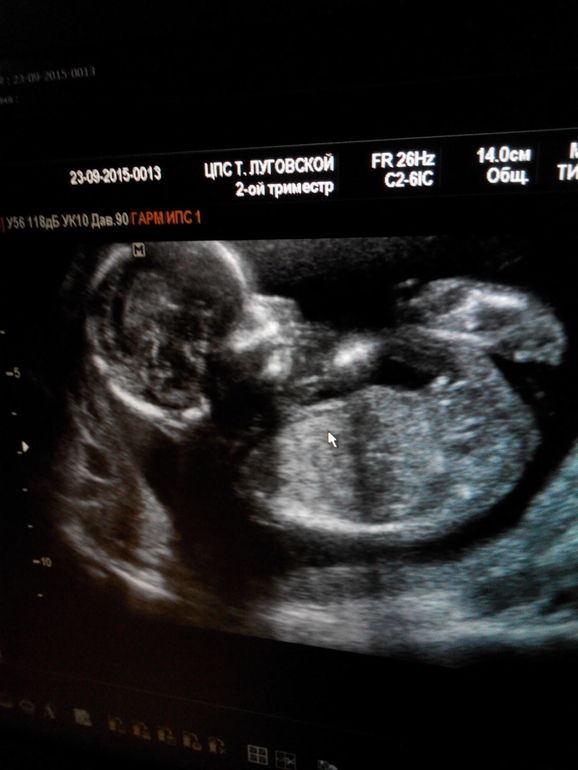

А у нас будет второй сыночек)

Вопросы про УЗИ, обследования и анализы: что, где, как, когда?Сегодня узнали,что мы ждем еще одного сыночка) муж думал девочка будет)

вот теперь аж не верю,что уже знаю что там сыночек второй)

по мес нам 17 недель,по узи 16.

Все у нас хорошо) будем думать имя)